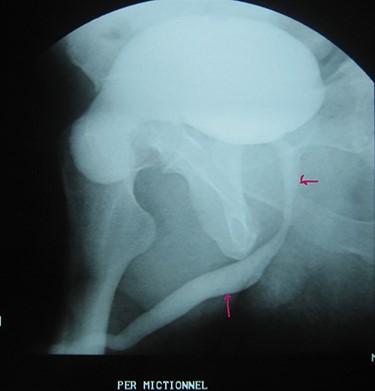

A 72-year-old man with a history of controlled diabetes and hypertension presented to our department with right inguinal swelling and intermittent lower urinary tract symptoms (LUTS) with pollakiuria, dysuria, prolonged micturition time and a sensation of a full bladder after micturition. He reported nausea, vomiting and right lower quadrant paint. The patient also reported having to manually compress the scrotum in order to empty the bladder. Physical examination revealed a slightly painful on palpation and reducible 6 cm right inguinal hernia extending into the right hemiscrotum. The body mass index of the patient was 31.4 kg/m2. His PSA was 4.3 ng/ml. On uroflowmetry, maximum flow rate (Qmax) was 13 ml/s and the voided volume was 180 cc. The uroflow curve was flat. The Bacteriological examination of urine was negative. Retrograde urethrocystography revealed right inguinal hernia containing a portion of the urinary bladder (Figs 1,2). He also had an intravenous urography in order to study the upper urinary tract and to have an idea of the renal function. This radiological exploration confirms the data of the retrograde urethrocystography and illustrates well the bladder hernia. However, a moderate left hydronephrosis with a nonobstructive pyelic calculus of 1.5 cm was observed on intravenous urography (Figs 3,4). Intraoperative findings revealed a direct right inguinal hernia with complete herniation of bladder into the scrotum. The bladder appeared healthy with no signs of injury and was restored to its normal anatomical position without resection. The hernia was repaired with a biologic mesh by the Lichtenstein technique. The patient had an uneventful postoperative course. Concerning his pyelic calculus problem, shock wave lithotripsy sessions were scheduled.

Urethrocystography: no obstruction under the bladder in the per mictional image.

Intravenous urography: moderate left hydronephrosis and bladder addition image.